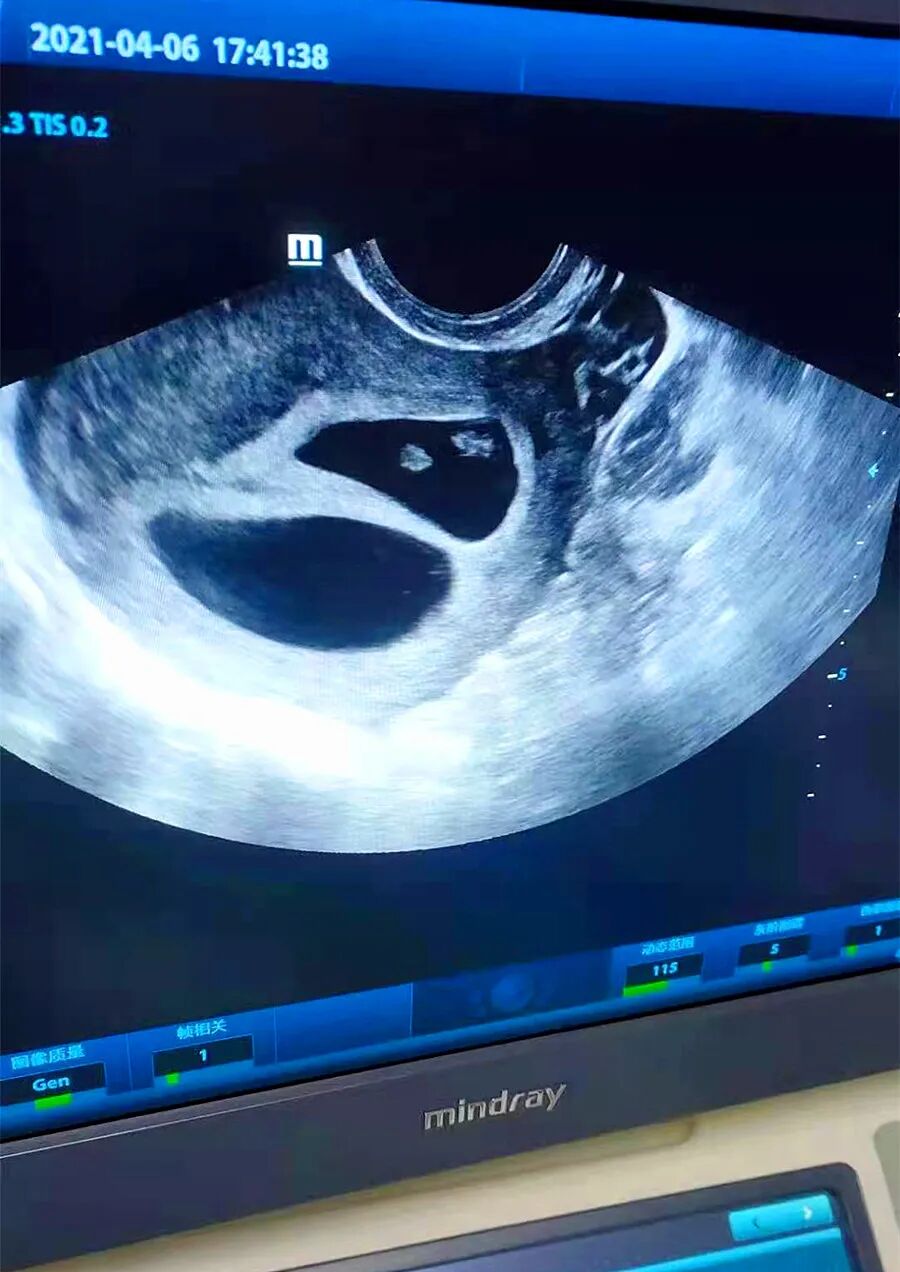

“朱院长,没想到您给我调理了才一个月就怀孕了,而且还是双胎,真是太感谢您了!”4月6日下午5时46分,当朱琳院长告诉不孕不育患者王女士已成功怀孕而且还是双胎时,王女士情不自禁地流着幸福的泪水连声向朱院长表达着真诚的感谢。

原来,今年35岁的王女士结婚多年,一直未孕,心里很着急,到处求医、吃药,可都没有见效。这次听朋友说蓝湾医院在治疗不孕不育上很不错,就抱着试试看的心情来了。今年3月初,夫妻俩就一起到蓝湾医院就诊,在朱琳院长一个疗程的精心调理后,王女士明显感觉自己的腰宽了好多,也比以前有力气了。就这样,经过一个多月的调理,这次彩超检查显示王女士怀孕双胎,夫妻俩多年的心愿终于要实现了。一朝怀孕,圆了多年的梦!喜悦和感激之情是无以言表的。